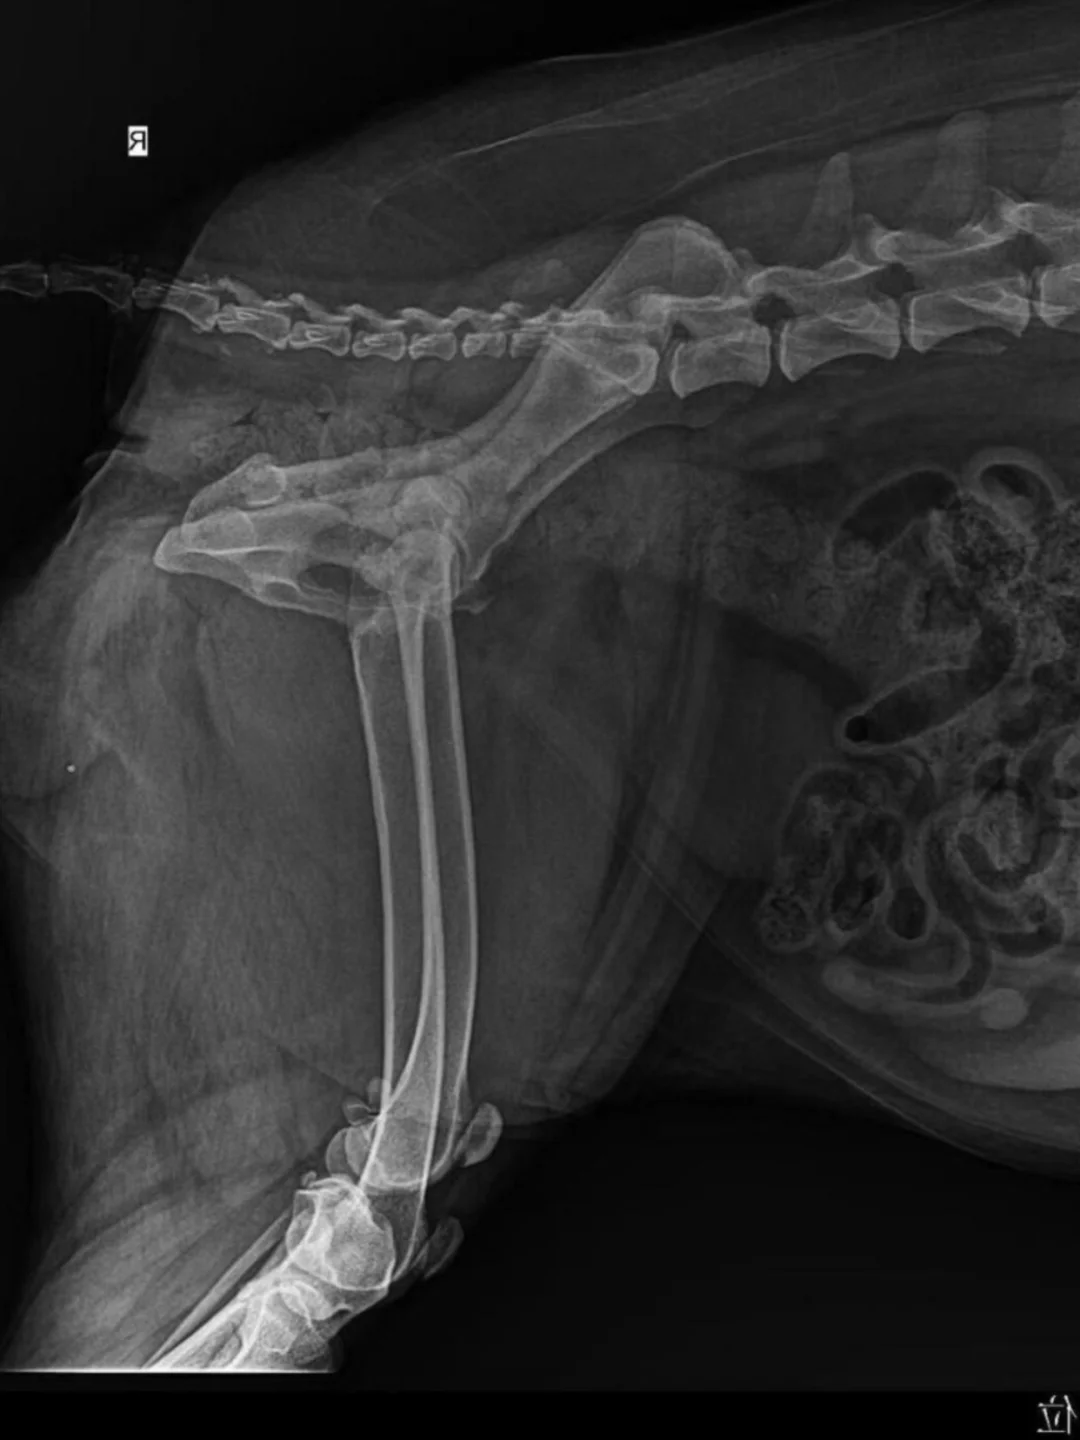

我当时特别焦虑,各种查资料咨询才知道老年犬关节炎看似是关节疼、僵硬,其实根源是软硬骨老化,硬骨增生、软骨磨损流失,长期摩擦会加重疼痛🦴甚至诱发骨刺。

前段时间带它复查,说软骨磨损没有继续加重,疼痛也明显缓解。